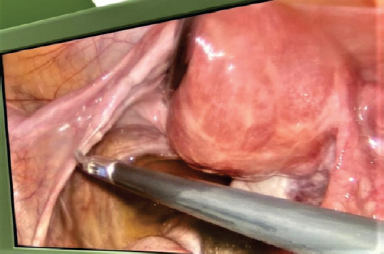

В нашем приведенном клиническом случае у пациентки 38 лет отсутствовали жалобы на момент госпитализации, но в анамнезе — постоянные сильные боли внизу живота на фоне полного благополучия. При ультразвуковом обследовании органов малого таза левый яичник не визуализируется. По данным магнитно-резонансной томографии органов малого таза обнаружено кистозное образование в позадиматочном пространстве с геморрагическим или высокобелковым содержимым, а также отсутствие визуализации левого яичника. При лапароскопии выявлена аутоампутация левых придатков матки вследствие перекрута, наличие некротизированного образования в позадиматочном пространстве. Таким образом, лапароскопия — это единственный достоверный метод диагностики и лечения перекрута придатков матки.